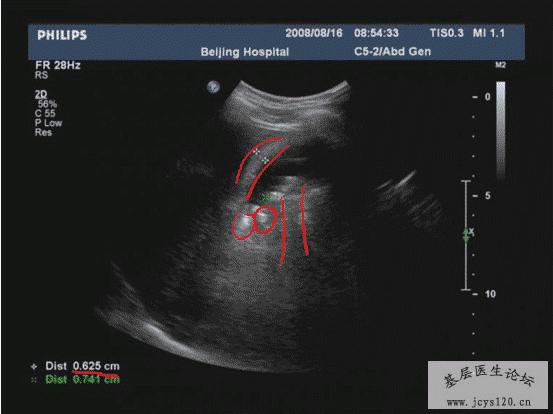

医学教育网讲义里面的精彩图片!